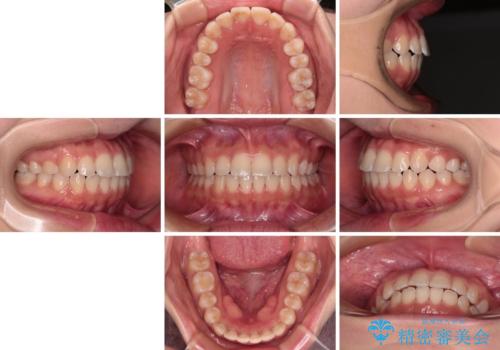

【モニター】短期間で終わりたい ワイヤー装置での非抜歯矯正

- 矯正装置

- 審美装置

- 1年1ヶ月

- 前歯のデコボコを気にして来院された患者様です。

マウスピース矯正のような自己管理の煩わしさがなく、早く治療を終えたいとのことで、ワイヤー装置による矯正治療を行うこととしました。

当初予定通り、1年で治療を終えることができました。

後戻り防止はマウスピースで行うため、急に自己管理が必要となるため、移動の最後をマウスピース矯正で行うことで、マウスピース非装着による後戻りリスクを回避する工夫をしています。